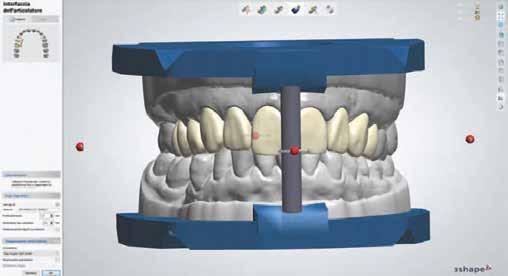

Úgy gondolom, egyre jobban. Ez mindenkinek érdeke, hisz a digitális lenyomatozás, a harapás digitális összeállítása a beszkennelt állcsontokkal és a számítógépes tervezés sok hibalehetőséget küszöbölne ki. Ha ehhez elviselhető árak is társulnak, robbanásszerű fejlődésre számítok. Azt gondolom, hogy a fejlődést nem lehet megállítani, és bár az alkotó szellemet nem lehet természetesen gépekkel helyettesíteni, minden arrafelé hat, hogy a különféle digitális technológiák még inkább átszövik a fogászat minden ágát. Az intraorális szkennerek, a CAD/CAM technológia, a 3D printing, a digitális artikulátorok további fejlődésével ezek a vívmányok –remélhetőleg – a rendelőkben egyre inkább elérhetőek lesznek, és rutinszerű alkalmazásuk még pontosabbá fogja tenni a mindennapi munkát. A digitális fogászatban különösen sok új lehetőséget láthatunk. A digitális technológiák évtizedek óta rendelkezésre állnak, de szakértelem és látásmód nélkül használhatatlanok, vagy egyszerűen nem érik meg a gazdasági befektetést. Szerintem ez a jövő útja!

14.00–15.30 Prof. dr. Marko Jakovac, Dragan Stolica (Horvátország): Digitális protokoll a minimálisan invazív fogászatban

terveztük a páciens igényeinek megfelelő harmonikus mosoly biztosításához szükséges fogformákat és az ínylefutást. A diagnosztikus wax-up szkennelését (D2000, 3Shape A/S, Koppenhága, Dánia) követően digitálisan megterveztük a sebészi sablont, és azt 3D nyomtató segítségével (Form 3, FormLabs) rezinből (Dental LT Clear Resin V2, Form 2, FormLabs, Somerville, Massachusetts, Egyesült Államok) elkészítettük (4. ábra). A sebészi sablon fogakra történő helyezését követően egyértelműen látszott, mely vonalban kell az

retében kijelenthetjük, hogy ez egy ígéretes technika lehet a fogak minimál invazív módszerekkel történő belső fehérítésére. A washi papír alkalmazásának további előnye, hogy megkönnyíti az ideiglenes zárás elkészítését. Az ideiglenes zárást biztosító anyag a fehérítő paszta nedvességtartalma miatt gyakran elválik a fog anyagától. Ha a pasztát washi papírba csomagoljuk, akkor jobban tudjuk kontrollálni a fogfelszínek nedvességtartalmát, ami előnyös az ideiglenes zárás elkészítése szempontjából. Jelen esetben az ideiglenes zárás jól funkcionált. A kezelés során nem észleltük az ideiglenes tömés széli zárásának elégtelenségére utaló jelek jelenlétét. A kívánt fogszín elérését követően elvégeztük az ínyplasztikát. A beszkennelt diagnosztikus wax-up vagy a csontnívó cone-beam komputertomográfiával végzett elemzése alapján korszerű sebészi sablonok készíthetőek, amelyek elősegítik az ínylefutás minél tökéletesebb korrekcióját. Annak ellenére, hogy már több közleményben is beszámoltak a 3D nyomtatással készülő sebészi sablonok koronahoszszabbítás – azaz az íny és a csontszövet formálására – során való fehasználásáról16,17, nem találtunk olyan közleményt, amelyben a sablont kizárólag az ínykontúr lefutásának módosítására használták volna. Jelen esetben a diagnosztikus wax-up szkennelése után a sablont pontosan megterveztük, majd rezin alapú anyagból kinyomtattuk. A 3D nyomtatást és a CAD/CAM technológiát egyre szélesebb körben alkalmazzák a fogászat különböző területein. Ennek oka, hogy ezek az eszközök egyszerű és gyors workflow-t tesznek lehetővé. Jelen eset ellátása során egy 3D nyomtatással készült, rendkívül pontosan illeszkedő sebészi sablont alkalmaztunk a műtét pontos kivitelezése érdekében. A sablon vékony anyagvastagsága jelentősen növelte a páciens komfortérzetét a beavatkozás alatt. Jelen esetben a digitálisan megtervezett sebészi sablont egy hagyományos gipszminta alapján készítettük el. Ez egy köztes lehetőség a teljesen analóg és a digitális munkafolyamatok között. A gyakorló fogorvosoknak

meg kell ismerkedniük a digitális lenyomatvételi technikákkal és a számítógépes tervezéssel, mivel a jövőben a teljesen digitalizált munkafolyamattal készülő sebészi sablonok kerülnek majd előtérbe. A digitális fogászati munkafolyamatokban kevésbé jártas kollégák számára jelenleg is nyitva áll az a lehetőség, hogy az általuk használni kívánt sablonokat gipszmintára történő direkt felviaszolás alapján készítsék el. Kiemelendő, hogy a hagyományos mintára digitálisan készülő nyomtatott sablon kifejezetten jól illeszkedett, így ez a módszer ajánlott a digitális fogászattal megismerkedni kívánó fogorvosok számára.